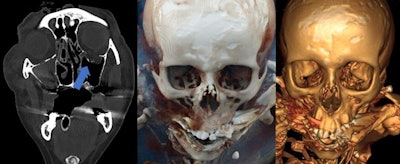

Between February 2016 and March 2019, Böven and her colleagues analyzed 112 fractures and injuries from 33 human cadavers (8 women, 25 men, with a mean age of 54 ± 18 years, range 31-92 years) that underwent whole-body postmortem CT after traumatic death. They reconstructed pathologies with CR and VR techniques, and classified fractures according to their dislocation.

Two forensic pathologists evaluated images according to their expressiveness and judicial relevance, and they decided whether CR reconstructions were suitable for judicial reviews. Two radiologists determined the detection rate of pathologies, and a traumatic cause of death was included.

CR was more expressive than VR for all three trauma categories (p < 0.01). Also, CR was more expressive than conventional CT when used for fractures with dislocation (p < 0.001), injuries of the ventral body surface (p < 0.001), and demonstration of foreign bodies (p = 0.033). CR and VR became more expressive with a higher grade of fracture dislocation (p < 0.001). In total, 20% of all pathologies in the CR and VR reconstructions were not detectable by radiologists.

In cases of fractures of smaller bones like the orbita or midface, forensic pathologists often found the CR and VR reconstructions not useful. A possible explanation could be lower digital resolution for smaller bones embedded in soft tissue.

- CR was more useful than conventional postmortem CT slices in cases of fractures with substantial dislocation, demonstration of foreign bodies, and body surface injuries not covered by other body parts or the CT table.